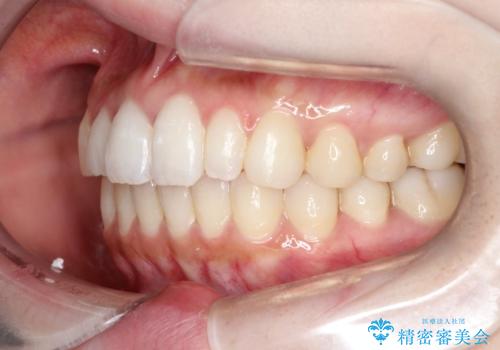

【インビザライン】矮小歯を有する方の治療②

- 前歯の凸凹を主訴に来院されました。

左上の前歯が元々小さいため、前歯の真ん中が揃わないことを伝えた上で矯正治療を開始しています。

スペースを作るために遠心移動ろIPRをおこなて治療を行いました。